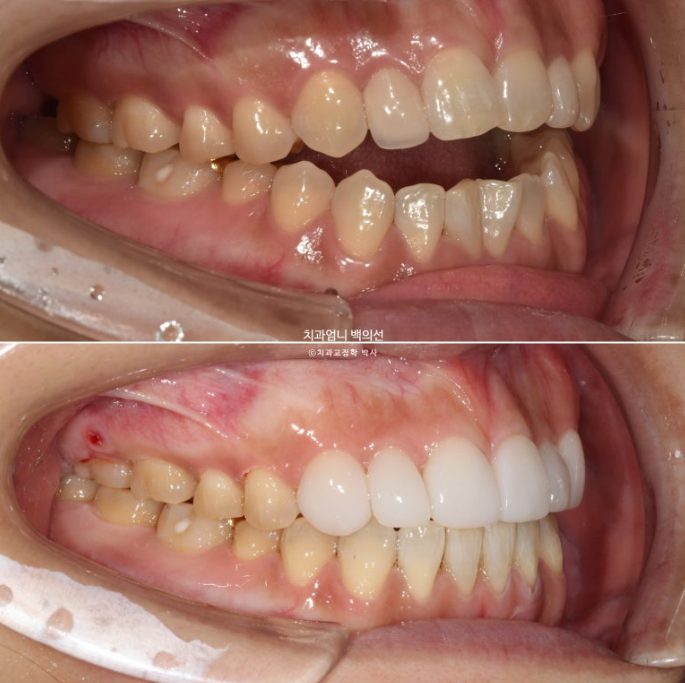

23.10

치료 시작 5개월차, 어금니 함입만으로도 앞니 개방교합이 많이 해소가 되었습니다.

사진에서 보듯이 어금니가 잇몸에 파묻히기 직전까지 함입을 시켰으니 이제 남은 개방교합은 앞니쪽에서 해결을 봐야죠. 이때부터 앞니를 정출시키기 위해 클리피씨 장치를 위아래 모두 부착했습니다.